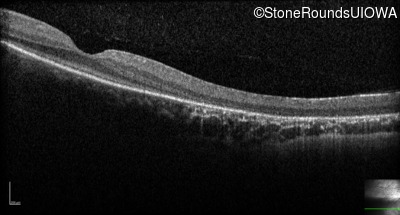

Optical Coherence Tomography - Left - No Light Perception

Exemplar / OCT Stack